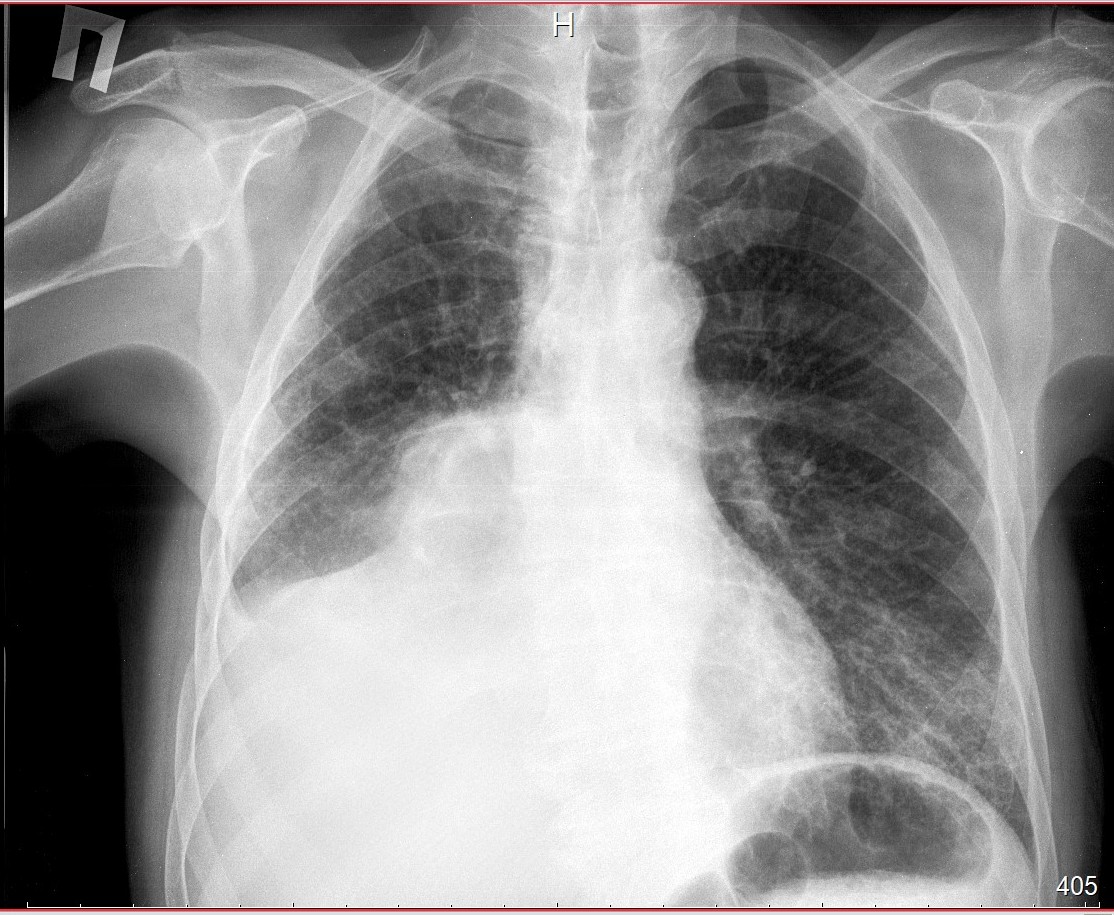

Что такое малоконтрастная рентгенограмма органов грудной клетки